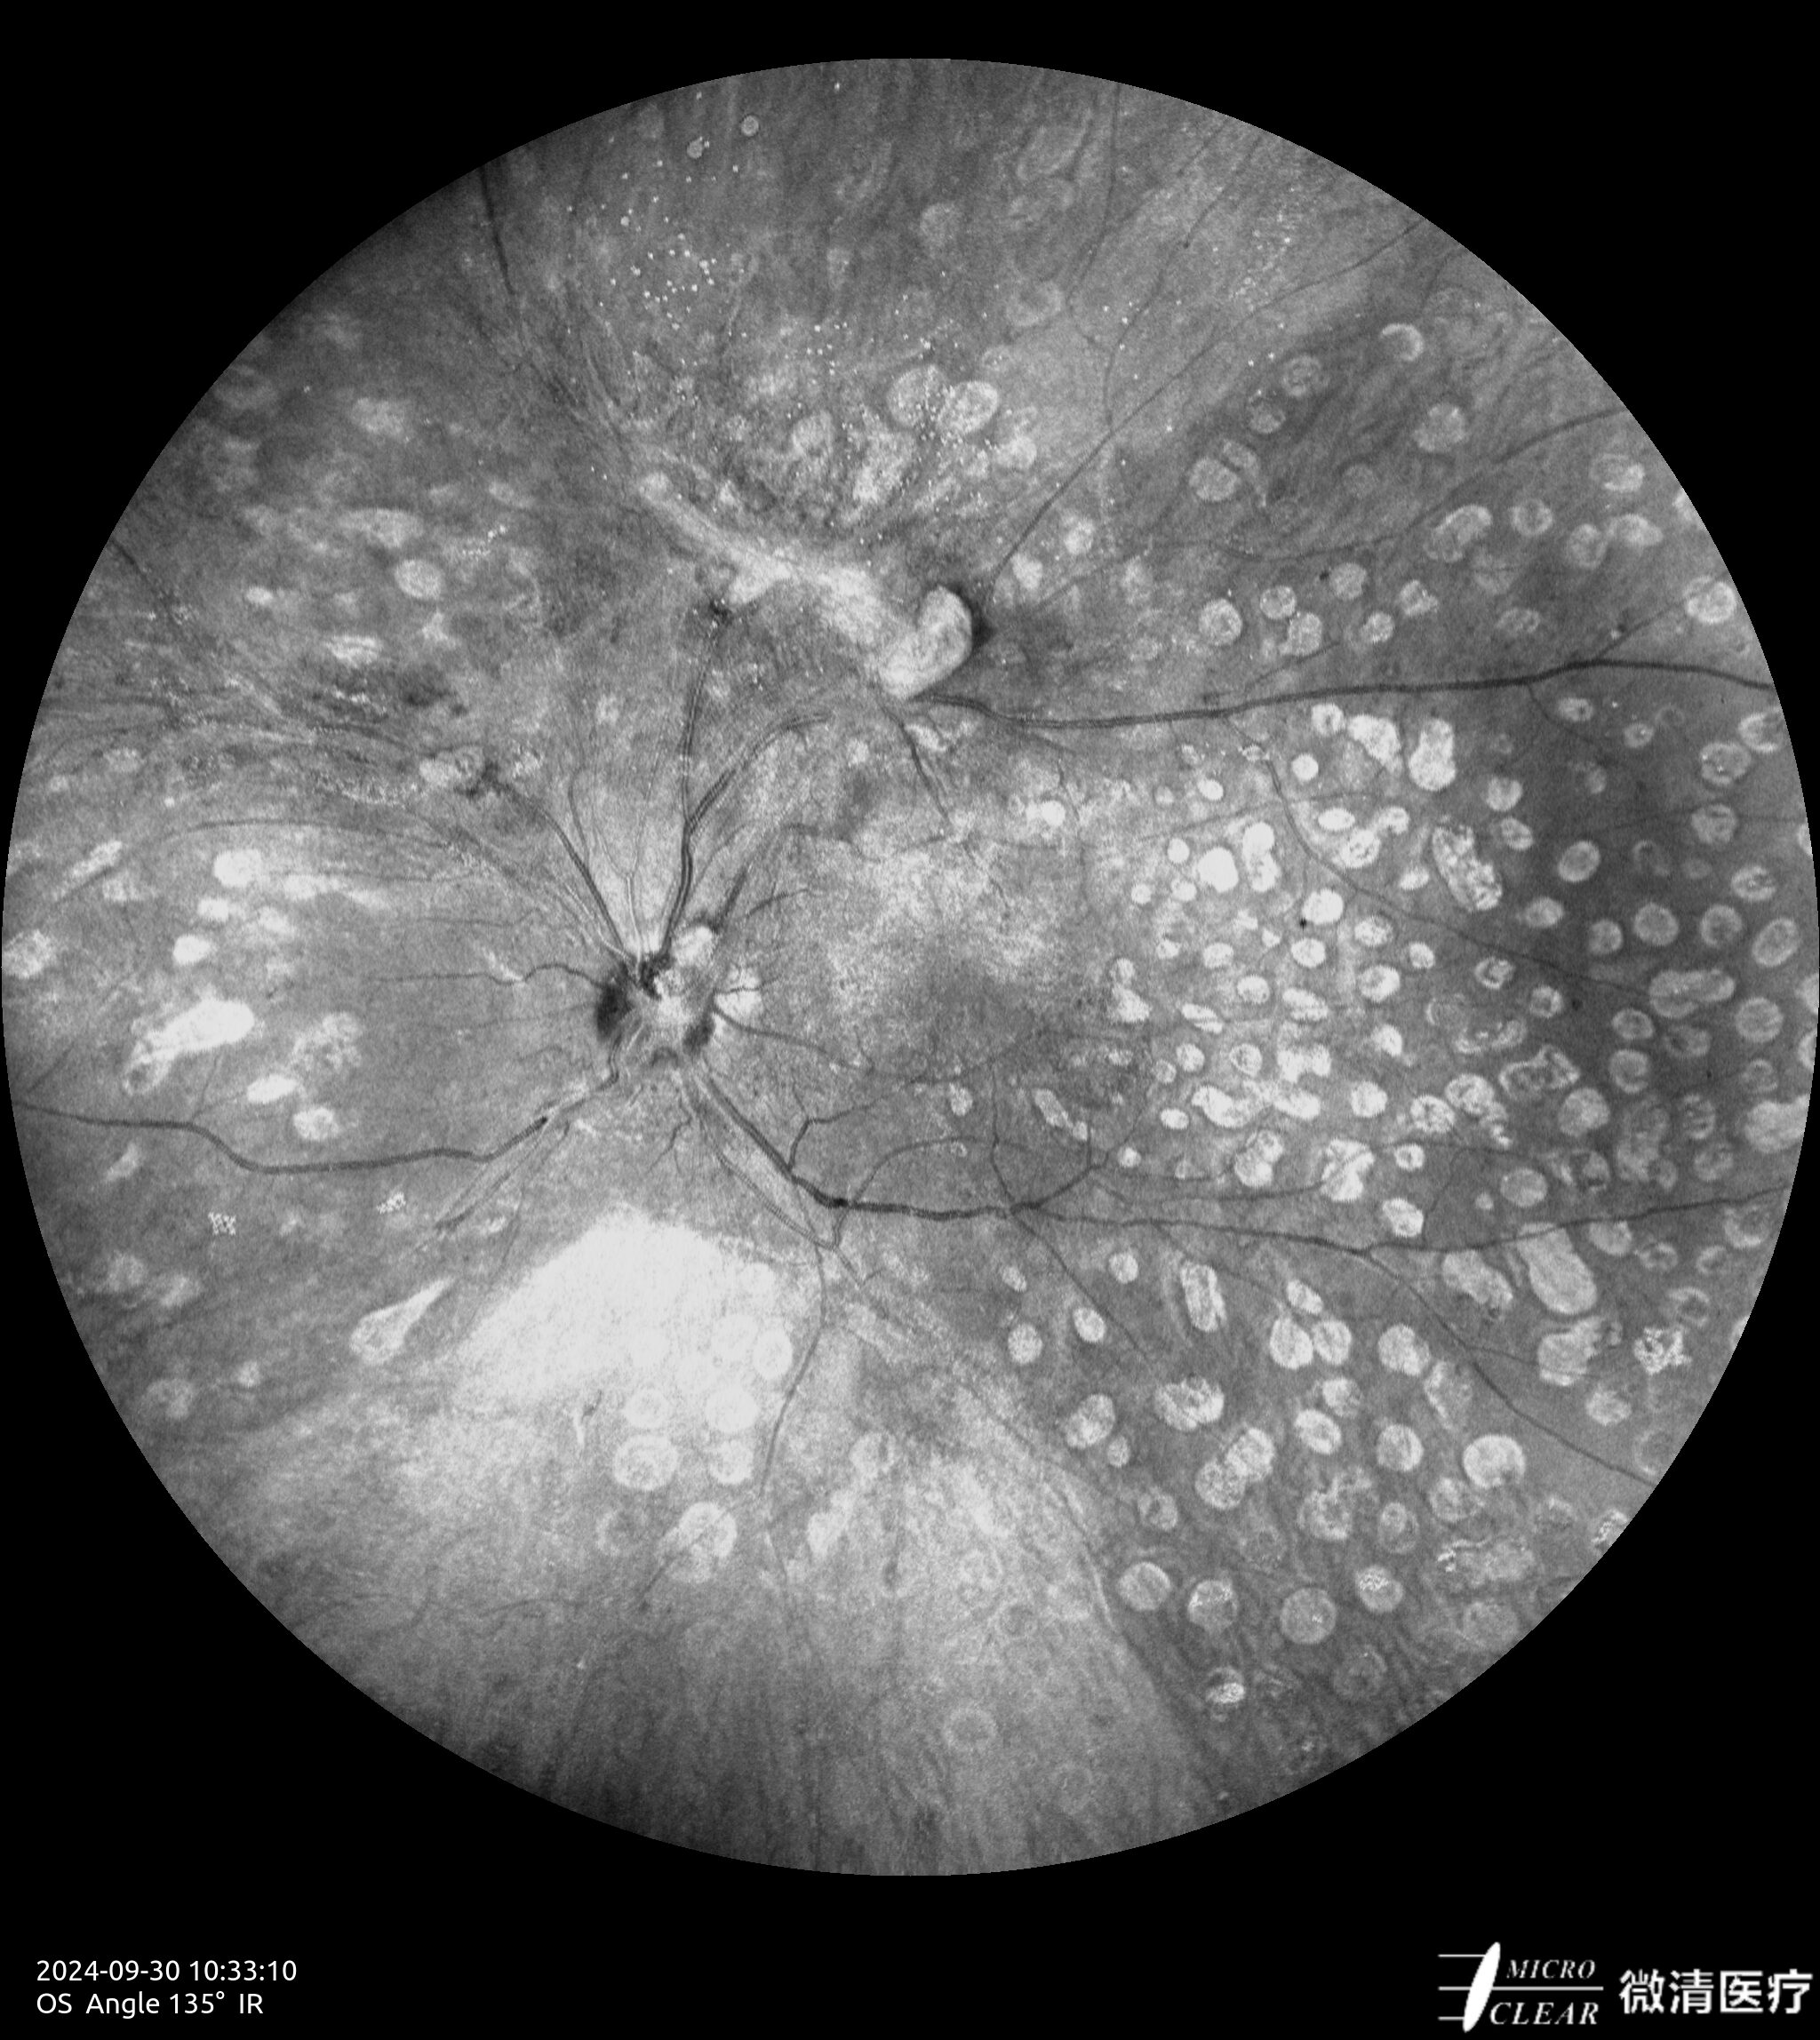

- 135° WA (Groothoekangiografie) – in één opname

Confocale Scanning Laser Oftalmoscoop (CSLO)

- Combinatie van drie confocale laserbronnen voor maximaal contrast en getrouwheid.

- Verbeterd confocaal ontwerp zorgt voor een betere scheiding van de netvlieslagen en verbeterde penetratie door cataract en oculaire troebelingen.